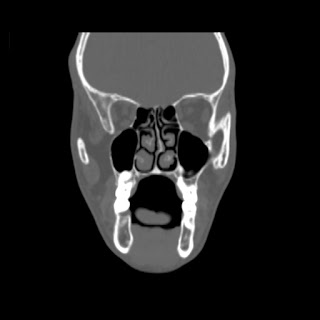

O/E images: